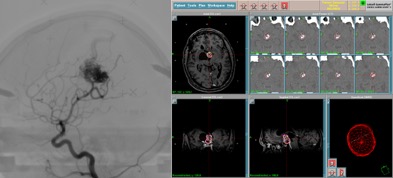

la radiochirurgie par Gamma-knife consiste à focaliser des photons de haute énergie (rayons gamma) au moyen d’un collimateur sur une ciblée petite taille ; les tissus traversés reçoivent une dose minime d’irradiation. On peut comparer le gamma-knife à une loupe qui permet de concentrer les rayons du soleil sur une feuille de papier : le papier brûle alors que la main placée entre loupe et le foyer ne sent rien.

il s’agit d’une méthode non invasive permettant de traiter une malformation arterio-veineuse par sclérose progressive des vaisseaux que la nourrissent.

l’efficacité est progressive et lente ; on estime en effet à 3 à 4 ans le temps nécessaire à la disparition de la MAV. En cas d’effet incomplet ou de récidive d’angiome, une radiochirurgie peut être de nouveau administrée (il n’y a pas d’effet cumulatif comme dans la radiothérapie)